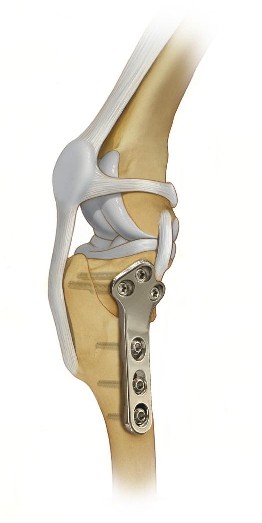

Tibial Plateau Leveling Osteotomy (TPLO)

TPLO Surgery

Geometry modifying procedures are most commonly done for dogs weighing over 40 pounds who may not achieve adequate stabilization with the more basic extracapsular repair technique. The most common surgeries within this category are the Tibial Plateau Leveling Osteotomy (TPLO) and Tibial Tuberosity Advancement (TTA).  The TPLO is the gold standard as it provides the best short and long term results of all Cruciate Ligament Repair surgeries. A TPLO involves cutting the tibia to change the slope of the joint, thus changing the mechanics within the knee to provide stabilization. Bone plates are placed on the newly cut bone to secure the angles and allow the bone to heal. These bone plates are generally left in place for the life of the dog.

The TPLO surgery offers excellent long term stabilization and functionality of the repaired limb and is the gold standard procedure for most large and/or active dogs.  A drawback of the TPLO is cost, as these are more expensive than the extracapsular repair surgery.